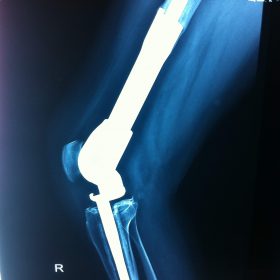

Σε αυτό το σημείο η Αρθροπλαστική Γονάτου αποτελεί μονόδρομο.